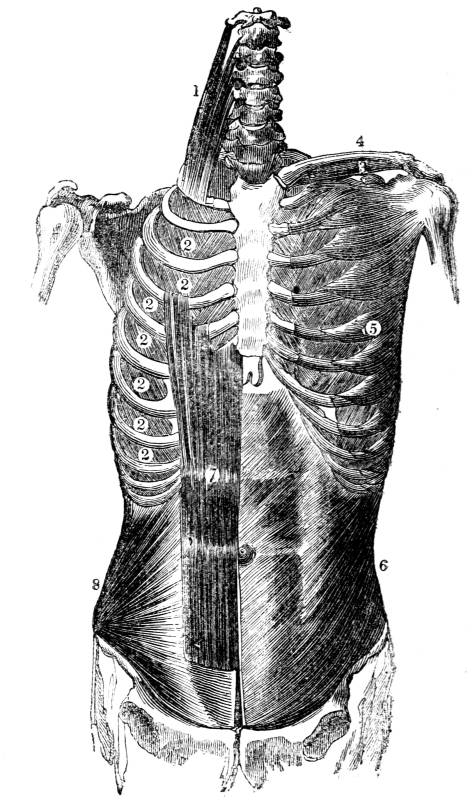

377. The osseous portion of the thorax, which

has been fully described (69 et seq.), consists of

the spinal column (fig. CXLI. 1), the ribs with their

cartilages (fig. CXLI. 2, 3), and the sternum (fig.

CXLI. 4). The soft portion of the thorax consists of

muscles and membrane (figs. CXLII. , CXLVI. , and

CXLVII. ), together with the common integuments of

the body. The chief boundaries of the cavity of the

thorax before, behind, and at the sides, are osseous,

being formed before by the sternum and the cartilages

of the ribs (fig. CXLI. 4, 3); behind by the

spinal column and the necks of the ribs (fig. CXLI.

1, 2); and at the sides by the bodies of the ribs.

Below the boundary is muscular, being formed by

the diaphragm (fig. CXLIII. 3).

Fig. CXLI.—

View of the osseous portion of the Thorax.

1. Spinal column. 2. Ribs. 3. Cartilages of ribs. 4.

Sternum.

380. The ribs form a series of moveable arches,

the convexity of the arches being outwards, and53

the whole being disposed in an oblique direction

(fig. CXLI. 2). The first rib springs from the ver54tebral

column at nearly a right angle (fig. CXLI.

2); the acuteness of this angle increases in succession

as the ribs descend from the first to the

last (fig. CXLI. 2); in this manner each rib is

inclined obliquely outwards and downwards, and

the obliquity thus given to the general direction of

the ribs augments progressively from above downwards

(fig. CXLI. 2).